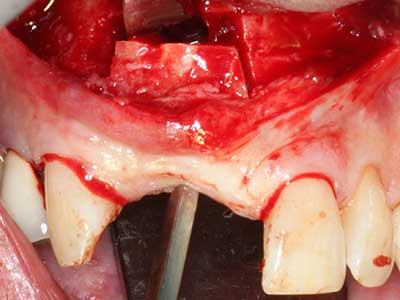

When surgical procedures are performed on bone in the immediate vicinity of sensitive structures such as blood vessels or nerves, rotary instruments pose a significant risk of iatrogenic injury. Piezoelectric devices can be helpful for preparation of bone covers and removal of hard tissue close to nerves, particularly for exposure of nerves after iatrogenic injury but also during nerve lateralization for resective and reconstructive procedures or implant placement (Fig. 17-20). Light contact between the piezotip and the nerve does not generally result in damage but proceeding incautiously with saw-like motions or attachments where a residual bone substrate remains may cause temporary or even permanent nerve damage. However, the risk of damage is considered to be substantially lower than when using saws or milling instruments (Pereira, Gealh et al. 2014).